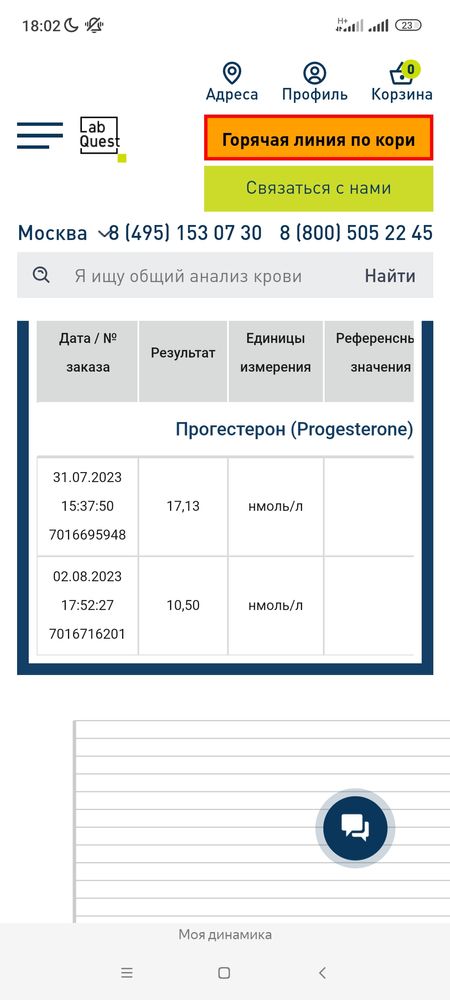

Мало или нормально?

Прогик вчера 10

До м сказали осталась где-то неделя,это я так понимаю прогестерон недостаточность или что?

Если 10 нг/мл то овуляция была, но для беременности маловато.. ждите М. А если 10 нм/мл то даже овуляции не было и очень маленький результат

Кулакова Александра, я не знаю вашей ситуации. И какой день цикла.. просто если бы вы сдавали на 7 дпо предположительно, было бы так как я выше писала. Но прогестерон низкий.

Смородинка, по УЗИ где то в этом районе,а сдавала прогик я получается раньше.

Это низкий результат прогестерона склоняюсь к тому что беременность исключена.